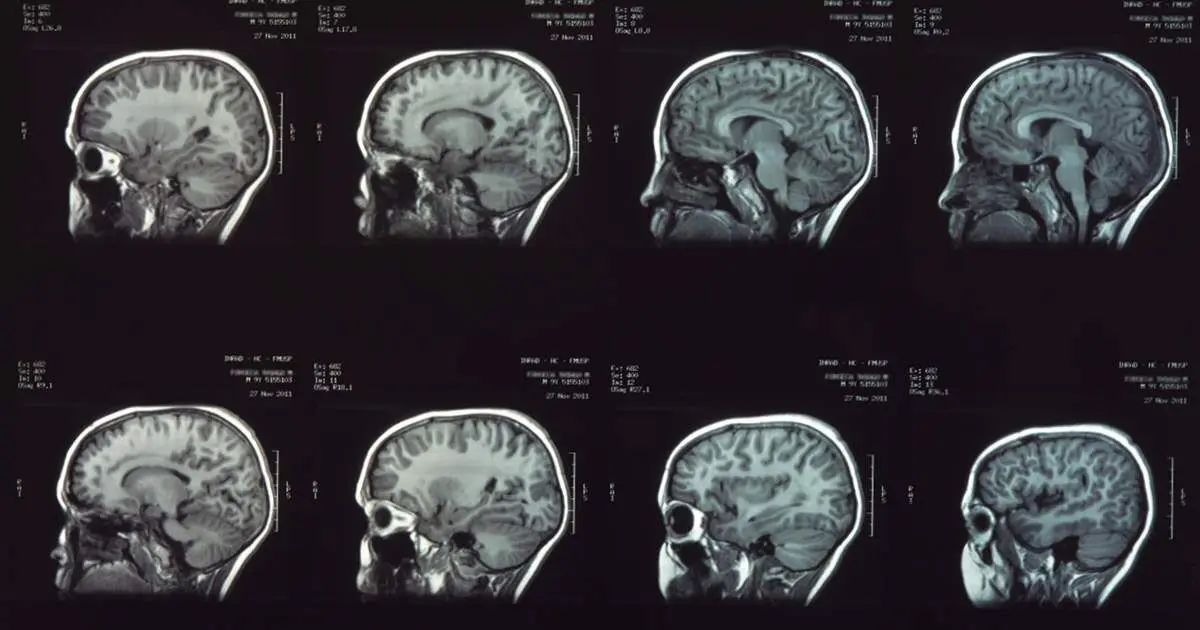

A descoberta, baseada na análise de 4 mil exames cerebrais de pessoas de 0 a 90 anos, ajuda a explicar oscilações no risco de transtornos mentais, no desempenho cognitivo e no surgimento de demência. O artigo Quatro grandes pontos de virada topológica definem cinco épocas do desenvolvimento do cérebro humano ao longo da vida foi publicado na revista Nature.